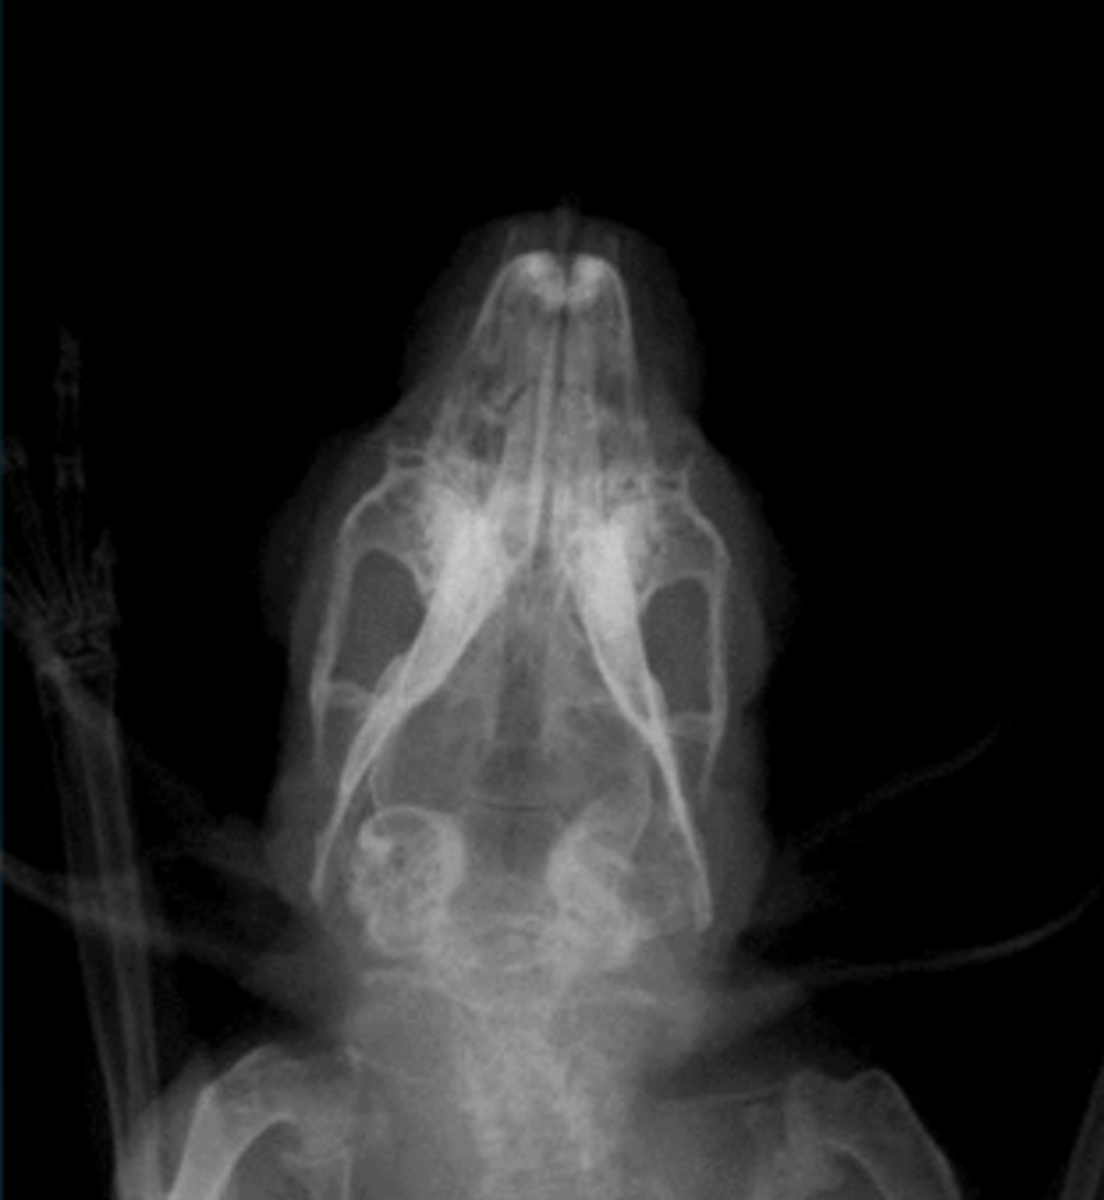

Otitis media and subsequent faical nerve paralysis

A rabbit presents with head tilt/torticollis. The rabbit also cannot blink. What do you think is going on based on this radiograph?